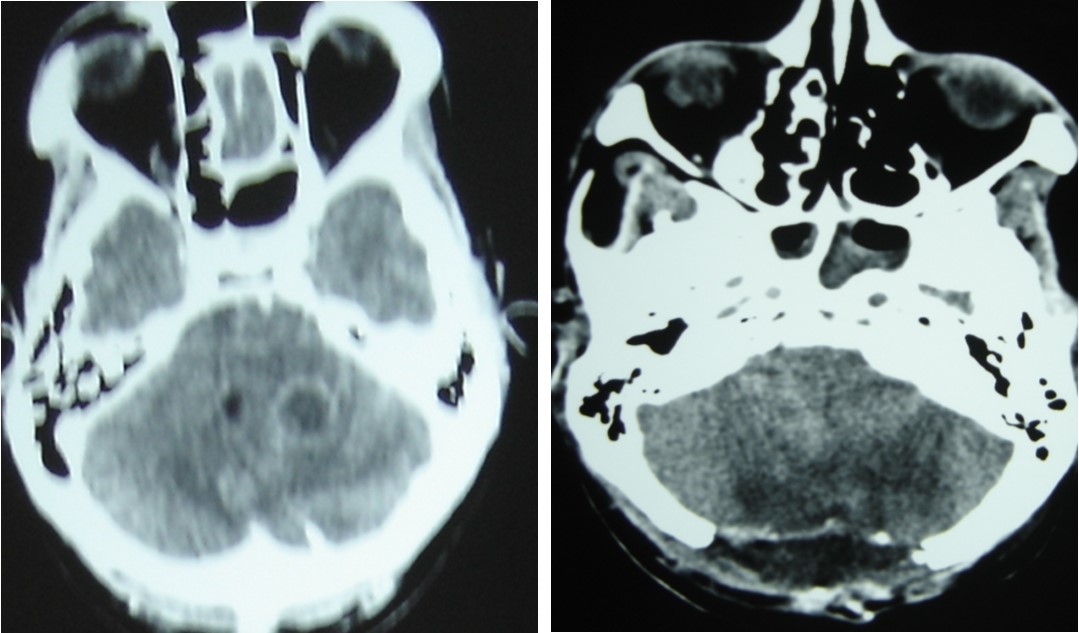

A 65 year-old man presented with progressive visual decrease and ptosis in the left eye. Neurological examination revealed paresis of the 3rd left cranial nerve. Fundoscopy revealed bilateral papillary paleness and visual acuity was: 4/10 at left; 7/10 at right. No signs of endocrine insufficiency or hypersecretion were assessed. There was no evidence of sinusitis. Chest X-ray, routine laboratory investigations and hormonal blood tests were normal. A CT scan showed a hypodense mass enlarging the sphenoid sinus and sellar region with calcification like images and bone erosion of the sellar floor (Figure 5). MRI showed a mass of 26 mm x 33 mm x 25 mm in the sphenoidal sinus ans sellar region, with hypersignal intensity in T1-weighted (Figure 6A) ans T2-weighted sequences, and hyposignal zone in T2-weighted sequences (Figure 6B). Imaging investigations were suggestive of unusual pituitary macroadenoma. The patient underwent a transnasal transsphenoidal approach for excision of the mass. A yellow-brownish gluey material with gummy debris was aspirated from the sphenoid sinus, which was completely cleaned. The sellar floor was eroded which allowed a view of the intact inflammatory dura. An intra-operative presumptive diagnosis was made of caseating granuloma (i.e tuberculosis). The post-operative course was uneventful: the patient recovered from ptosis and visual acuity improve at discharge. Mycobacterium tuberculosis could not be cultured from specimens; and cultures on Sabouraud’s medium did not isolate Aspergillus. Pathologic findings were of non invasive aspergillosis, with many septated fungal hyphae being present without tissue invasion. The patient was not given antifungal drugs because the intrasphenoidal material was completely aspirated. At 6 month and 18 months follow up, the patient had no neurological complaint. No recurrence was observed on control CT scans.

Figure 5.CT scan showing a hypodense mass enlarging the sphenoid sinus and sellar region with calcification like images and bone erosion of the sellar floor